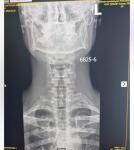

Здравствуйте. На rg-граме шоп двух проекциях костно-деструктивных изменений не определяется. Физиологический лордоз сглажен. Уплотнение замыкательных пластин тел позвонков, контуры их чёткие, ровные. Остеофиты по передним углам тел позвонков в блоке с4-с6, высота мпд снижена. Заострение крючковидных возвышений. Формирование патологического кифоза в блоке c4-c6. Заключение: РГ признаки распространённого остеохондроза первой степени. Ограниченный дефспондилёз первой степени в блоке c4-c6. унковертебральный артроз.